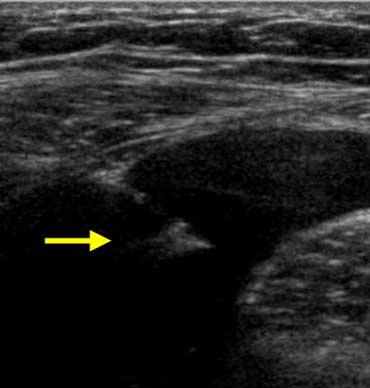

Lâm sàng nghi viêm ruột thừa. Siêu âm chỉ phát hiện một lượng nhỏ dịch cổ trướng. Chọc dò chẩn đoán (mũi tên chỉ đầu kim) cho thấy dịch máu. Ở phụ nữ, phát hiện này rất nghi ngờ thai ngoài tử cung (EUG).

Cổ trướng

Người tình nguyện khỏe mạnh không có lượng dịch tự do trong ổ phúc mạc có thể phát hiện được, ngoại trừ một lượng nhỏ dịch tình cờ ở túi cùng Douglas ở phụ nữ trong độ tuổi sinh sản.

Sự hiện diện của cổ trướng là dấu hiệu không đặc hiệu của bệnh lý ổ bụng, cho thấy ‘có điều gì đó bất thường’.

Có thể cân nhắc thực hiện chọc dò dịch cổ trướng dưới hướng dẫn siêu âm để xác định bản chất dịch: dịch phản ứng vô khuẩn, mủ, máu, nước tiểu hay dịch mật.